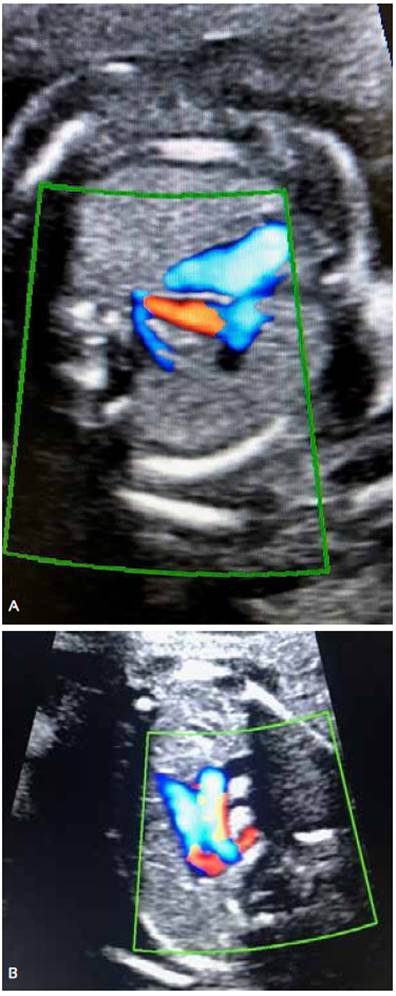

At 20 weeks of pregnancy, fetal anatomy ultrasound showed at the level of the three vessels and trachea, a retrotracheal vessel with suspicion of an aberrant right subclavian artery. No other cardiac or extracardiac structural alteration was identified. Sex was masculine. Figures 2 A and B.

Figures 2 A and B. Ultrasound evaluation at the three-vessel view section using color Doppler shows the corresponding retrotracheal vessel with ARSA.